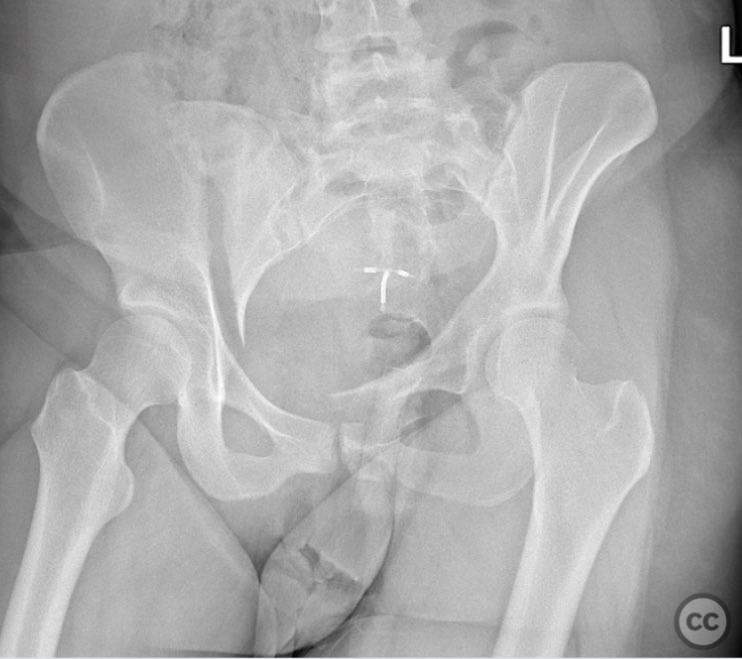

Clinical and radiological findings:  A 26-year-old female sustained a closed pelvic ring injury following a motor vehicle accident. She was hemodynamically stable, neurologically intact, and had no other associated injuries. Skin integrity was preserved. Initial management included pelvic binder application and 10 pounds of distal femoral skeletal traction. Portable AP pelvic radiograph demonstrated a left-sided sacral fracture with associated ipsilateral iliac wing and pubic ramus fractures, consistent with an AO/OTA 61-B2 (lateral compression type II) injury pattern.

Orthopaedic implants used:   Two 7mm diameter cannulated fully threaded medullary screws (iliac crest and pelvic brim), percutaneous iliosacral screw(s).